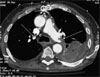

Ja, sogar sehr oft ! Die allermeisten Untersuchungen der Wirbelsäule, des Skelettsystems, der Gelenke, der Zähne und Nasennebenhöhlen kommen ohne Kontrastmittel aus. Bei Untersuchungen des Gehirns, der Halsweichteile, des Brust- und Bauchraumes und der Blutgefäße muß dagegen meist Kontastmittel gegeben werden, um eine optimale Aussage zu erhalten.